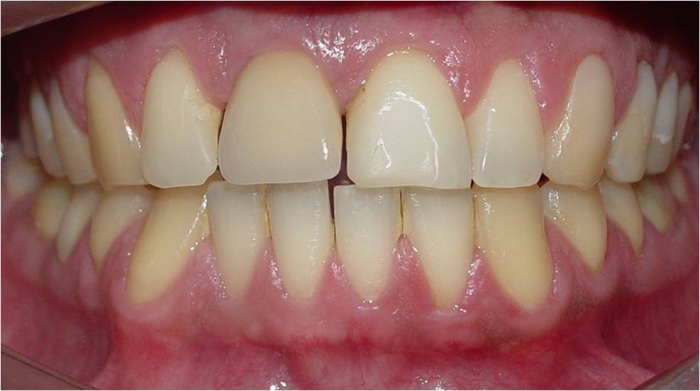

Prótese fixa de porcelana sobre o implante

Imagem do caso terminado em fevereiro de 2008